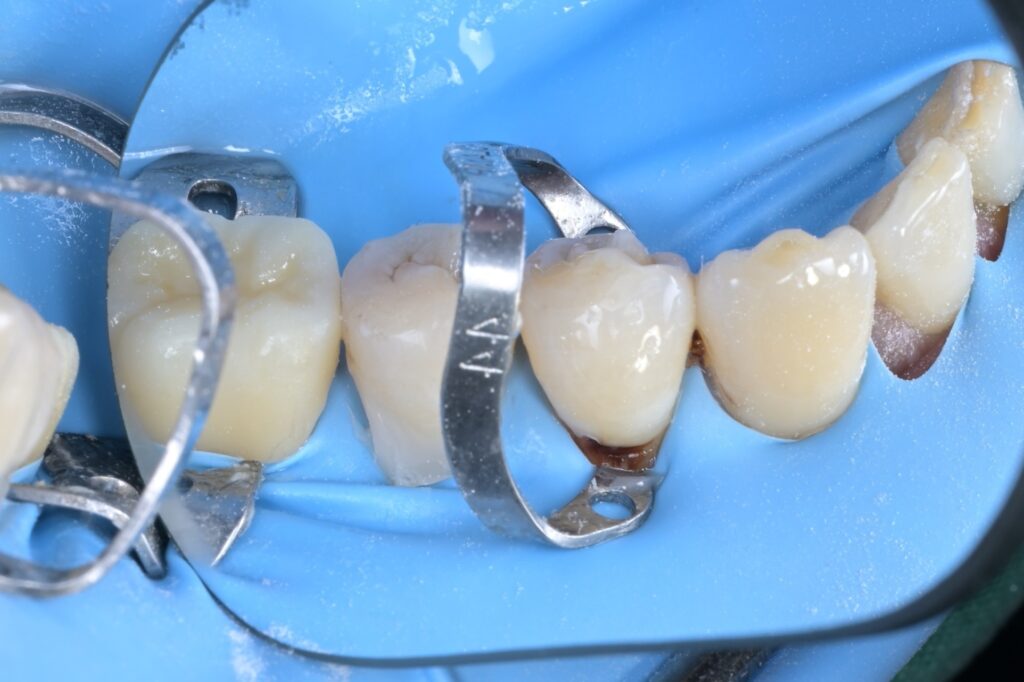

STEP 4 ~ 5. 앞쪽 치아 격리 (클램프 장착)

이제 앞쪽에 있는 제1소구치(4번)와 송곳니(3번)를 치료할 차례입니다. 이 부위는 잇몸 라인이 더 깊기 때문에, 잇몸을 살짝 아래로 내려주는 특수 클램프(금속 고리)를 각각의 치아에 걸어줍니다.

"원장님, 이렇게까지 해야 하나요?"

네, 해야 합니다. 저 금속 고리가 잇몸을 살짝 밀어줘야 치료할 부위가 확실히 보이고, 접착제가 잇몸에 닿지 않아 치료 성공률이 높아집니다.